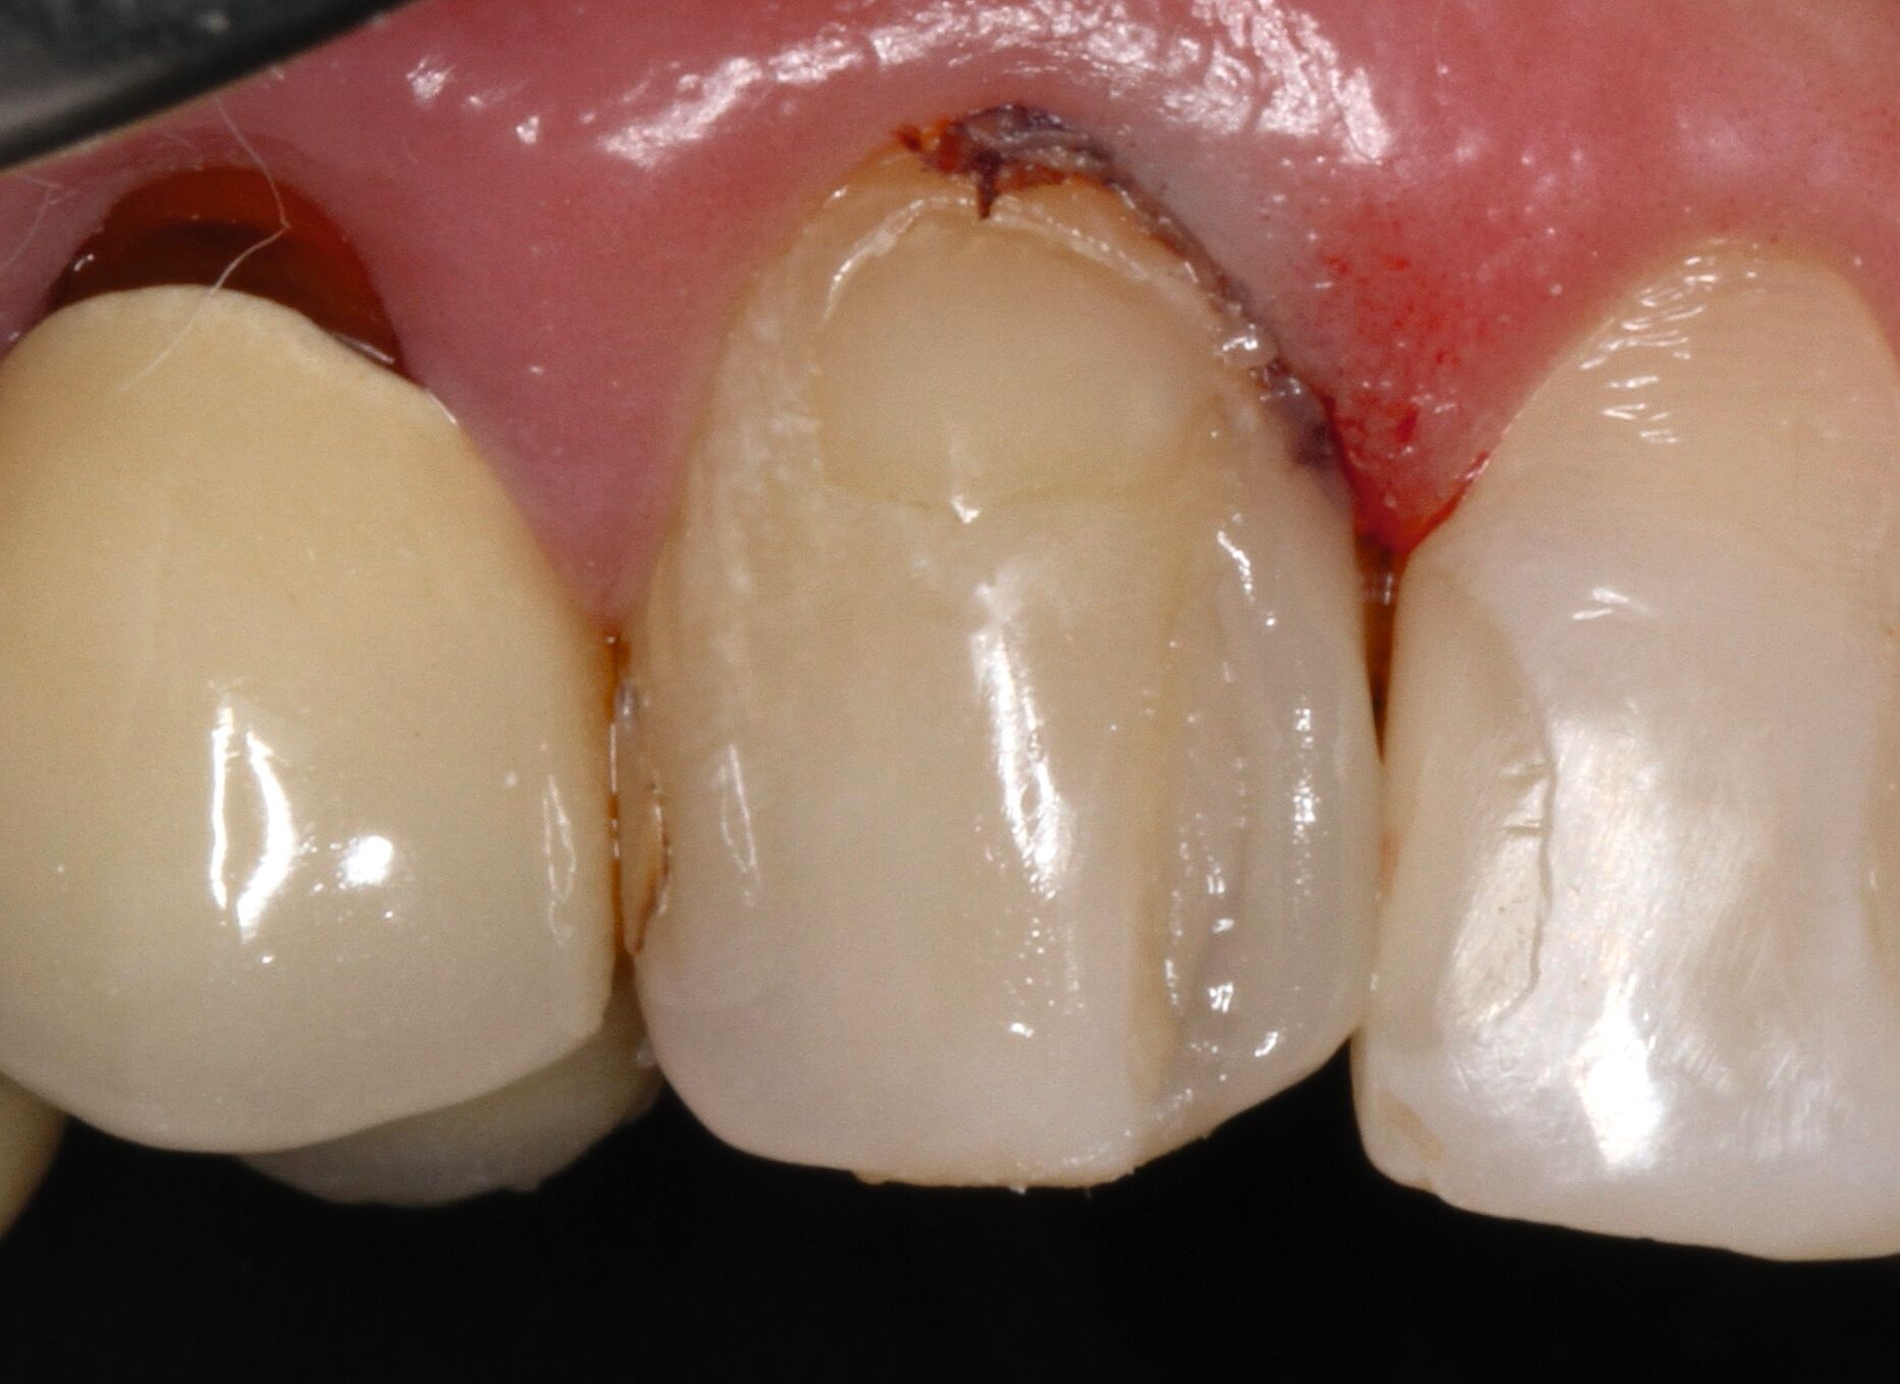

Die dentale Ausgangssituation zeigte im Seitenzahnbereich ein suffizient konservierend und prothetisch versorgtes Gebiss der zweiten Dentition sowie im Frontzahnbereich nicht kariogene Zahnhartsubstanzverluste und eine defekte Krone mit Sekundärkaries (Abbildungen 1 und 2).

Zur Verbesserung der Ästhetik und des Wohlbefindens des Patienten standen die Harmonisierung der Lachlinie und des Frontzahnbogens sowie Farb- und Formkorrekturen der Oberkieferfrontzähne im Fokus. An den Zähnen 11 und 21 waren Zahnhartsubstanzverluste durch Erosion und Attrition zu erkennen. Zahn 23 hatte ebenfalls einen erosiven Defekt, Zahn 13 eine farblich abweichende Kompositrestauration und die Zähne 14 und 24 wiesen keilförmige Defekte zervikal der Kronenränder auf, die einen suffizienten Randschluss haben (Abbildung 1a).

Vor 25 Jahren hatte der Patient ein Frontzahntrauma an Zahn 22 erlitten, der daraufhin mit einer Wurzelspitzenresektion und einer retrograden Amalgamfüllung versorgt worden war (Abbildung 3a). Dabei war die Zahnkrone mit einer keramisch verblendeten Stiftkrone aus Nichtedelmetall rekonstruiert worden, die nun aufgrund von Sekundärkaries insuffizient und gelockert war, jedoch keine Beschwerden verursachte. Klinisch wies der Zahn eine sehr kurze klinische Krone ohne ausreichendes Ferruledesign auf (Abbildung 5a) [Naumann et al., 2018a; Naumann et al., 2018b]. Neben dem Verdacht auf einen obliterierten mittleren Wurzelkanalabschnitt gab es röntgenologisch keinen Hinweis auf apikale Osteolysen oder parodontale Auffälligkeiten (Abbildung 3b). Der Patient entschied sich trotz des erhöhten Zahnhartsubstanzdefekts für den Zahnerhalt durch einen adhäsiv verankerten Kompositaufbau.